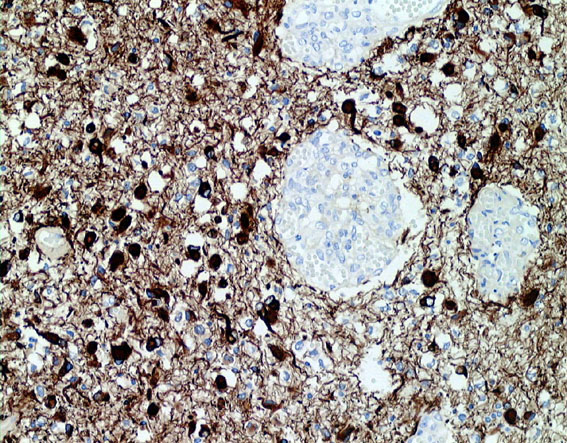

病理像です。左側の部分はperinuclear hallowが多い典型的な乏突起膠腫です。右側の部分ではびまん性星細胞腫の像ですが,その中に乏突起膠腫に特徴的なchicken wireと呼ばれる細い血管網も見られます。乏突起星細胞腫と呼ばれるのですが、腫瘍性格は乏突起膠腫と同じもので,星細胞系腫瘍には入りません。1p/19q欠失があるもののIDH変異がないのでoligoastrocytoma, NOSです。